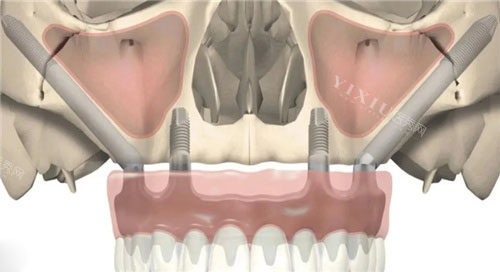

穿颧穿翼种植牙作为口腔种植领域的“技术”,专为上颌骨重度萎缩、骨量不足的患者设计。这项技术通过将种植体植入颧骨或翼板骨,实现“无土栽培”般的稳固结果,但价格也因技术难度和材料成本较高。

手术复杂度:单纯穿翼板种植(单侧约10万元起)比穿颧骨种植(单侧约12万元起)更简单,若需双侧操作或结合常规种植体,费用可能翻倍。例如,上颌半口穿颧+穿翼组合方案,价格普遍在20万元左右。

全口穿颧穿翼种植牙的起步价约10万元,但主流方案集中在28万~40万元,部分一线城市高端机构报价可达45万元。具体费用受以下因素影响:

手术方案:

基础方案:上颌穿颧穿翼+下颌ALL-ON-4(即刻负重)约25万30万元。

高端方案:上颌双侧穿颧+下颌ALL-ON-6(更稳固)约30万40万元。